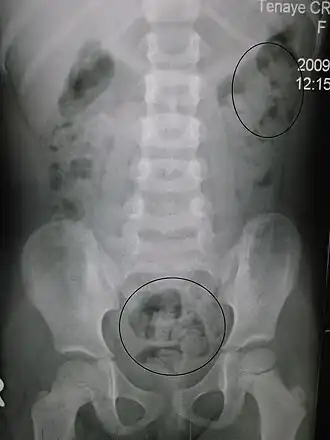

| Рентгенограмма запора у ребёнка. Кругами отмечены каловые массы (фекалии — белым цветом, окружающий их кишечный газ — чёрным цветом) | |